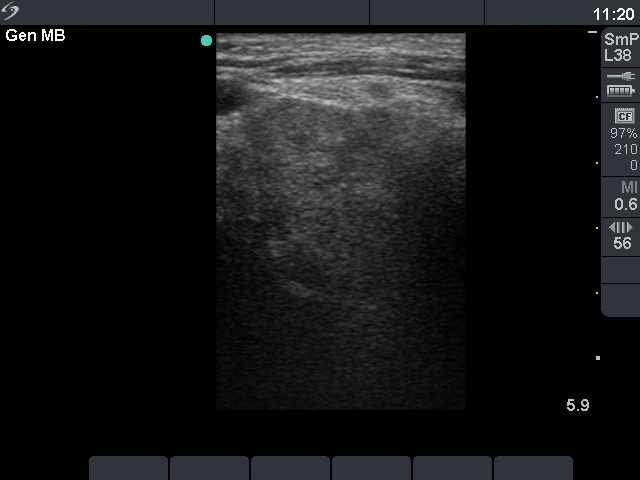

Ultrasonography. Both lobes were extremely enlarged with a maximal diameter greater than 13 cm. Both lobes spread substernal and retrotracheal. The thyroid was composed of multiple hypoechogenic nodules with only a small intact part. The nodules contained hyperechogenic areas corresponding to necrosis.